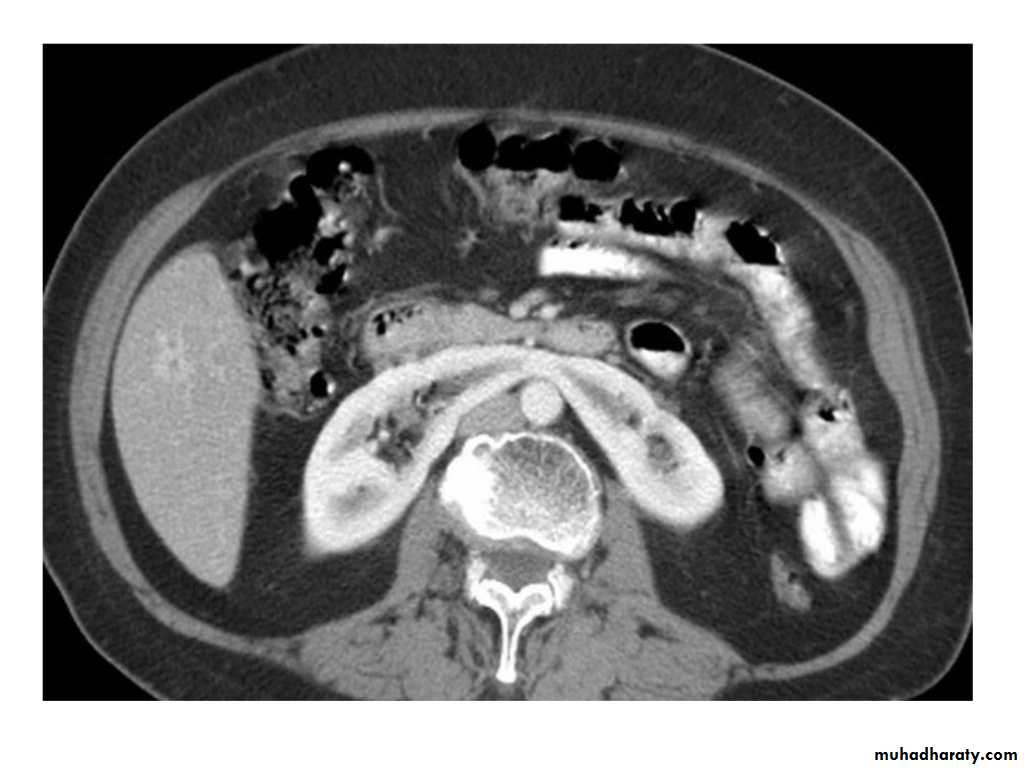

IVU shows

1. The kidneys at low position .2.Close to the spine with long axis parallel to the spine

3. Malrotation manifested by medially directed calyces.

4- The renal pelvis and ureters are anterior and lateral in position.

5- Hydronephrosis and calculi highly associated.